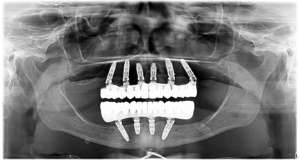

În timpul intervenției chirurgicale i-au fost inserate 6 implanturi dentare premium la maxilar și 4 la mandibulă. Apoi, după ce ne-am asigurat că operația s-a vindecat integral, am fixat dantura finală din Zirconiu pe o structură din Titan.

Zirconiul reprezintă standardul de calitate în reabilitarea dentară în ceea ce privește durabilitatea în timp și estetica. Mai multe detalii despre danturile finale realizate în clinica noastră puteți afla accesând: https://www.youtube.com/watch?v=xhxITRG0cZU